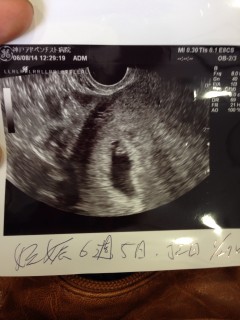

2週間ぶりの診察。 心拍を確認しとりあえず安心しました。 二人目でも内診は本当に緊張します。 そして、今日は排卵日と出産日が分かりました。排卵日が結婚記念日だったようで何だか嬉しかったですww